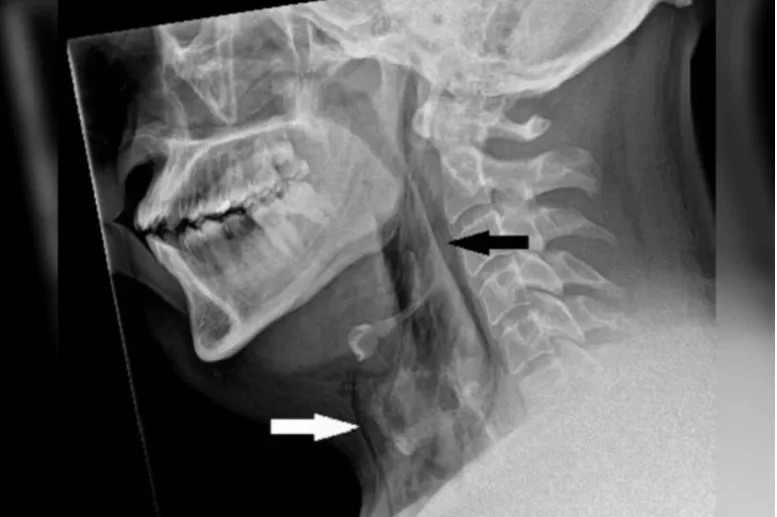

Após isso, o homem sentiu fortes dores no peito sendo obrigado a ir a um hospital em busca de atendimento de emergência. Um exame de imagem identificou a ruptura na traqueia de aproximadamente quatro milímetros.

“É raro, mas o acúmulo rápido de pressão na traqueia ao espirrar com o nariz apertado e a boca fechada ocasionou um rasgo traqueal, conforme os exames realizados no hospital de Dundee mostram”, destaca o texto da equipe médica.